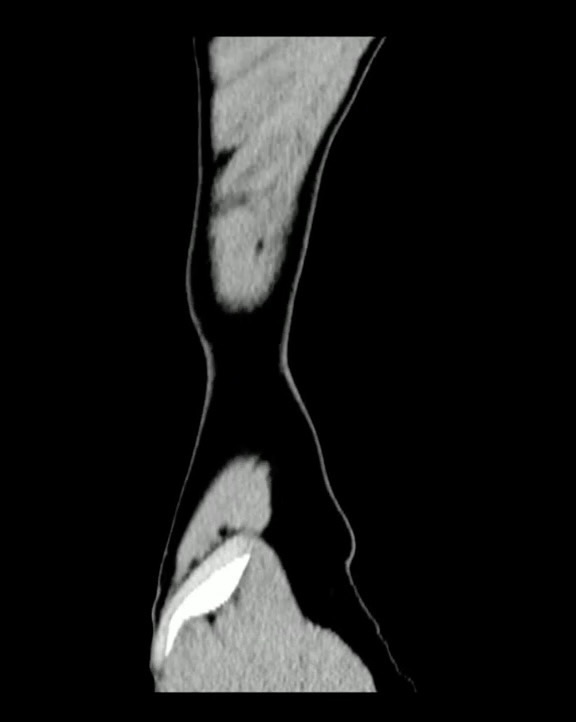

【腹盆】患者1小时前从高约2米处摔下,腹部硌到小区锻炼用的单杠上了。男,10岁。

【患者信息】:男,10岁。

【主诉】:患者1小时前从高约2米处摔下,腹部硌到小区锻炼用的单杠上了,伤后自觉腹痛。无恶心、呕吐。